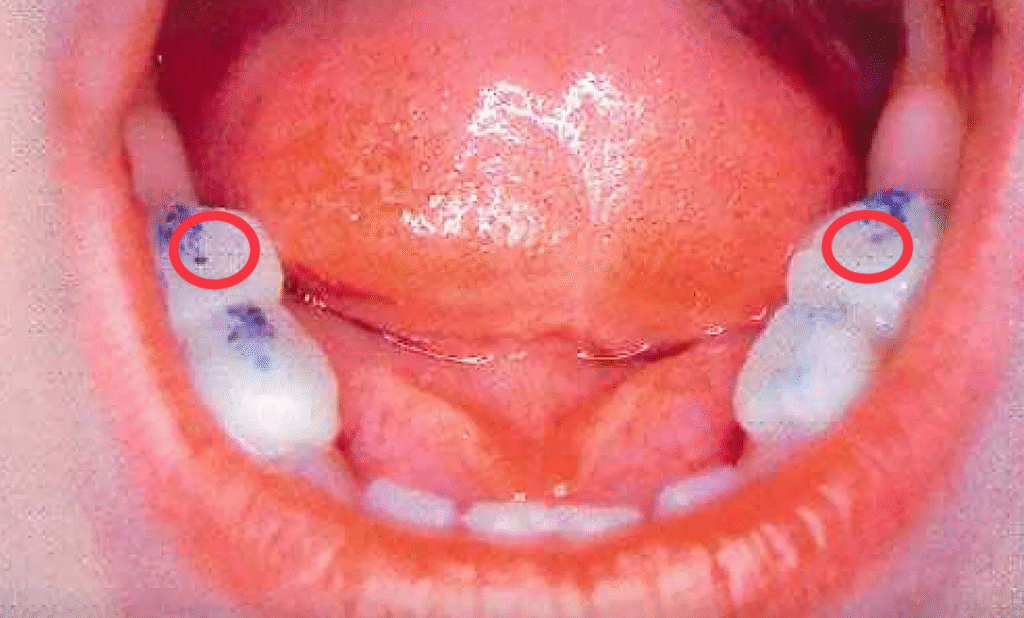

我們當時在泰國找了一位牙醫,在孩子左右兩邊最後面的乳牙(下圖紅圈標示處)表面各加了 3~4 毫米厚度的樹脂,而且樹脂頂部做得完全平坦,避免對咬的牙齒咬合卡死。

醫生墊高的程度,是讓孩子門牙前面形成了 2~3 毫米的咬合間隙。整個處理大概花了 20 分鐘,在泰國這邊費用大約等同 50 美金。